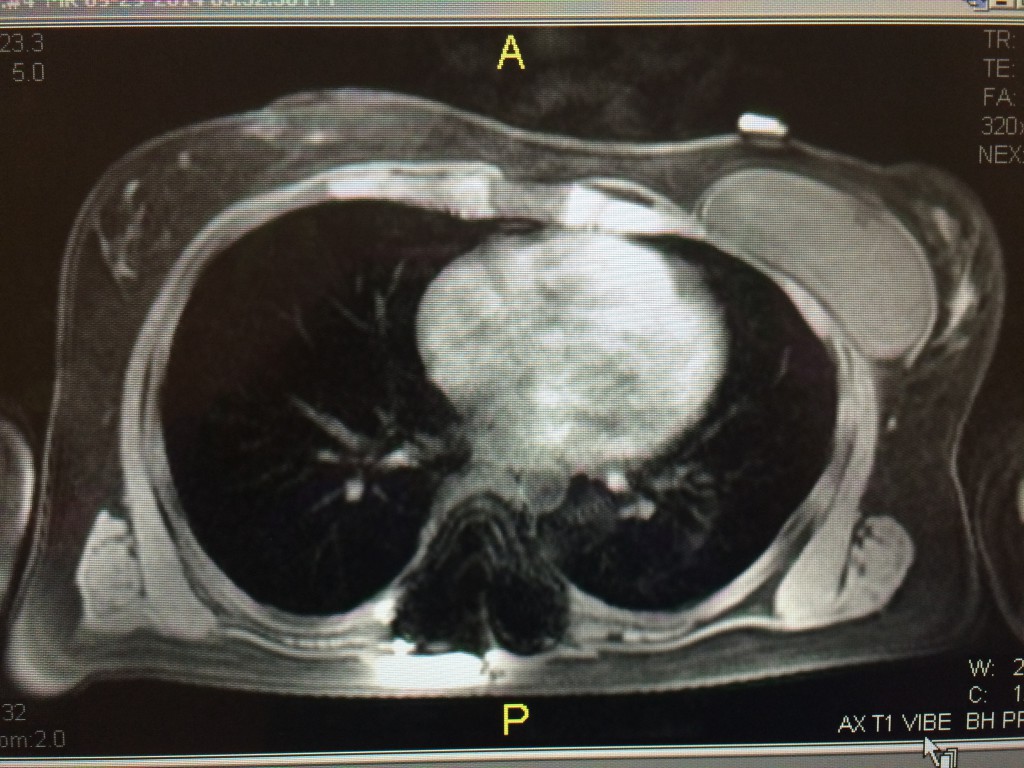

My issues started 3 months post-op with chest pain. I had severe chest pain on my left side only. I was supposed to begin Schroth PT around the time I began having pain. I was in and out of my surgeon and then a pain management doctor's office as I could not do my physical therapy activities without significant pain and discomfort. My pain doctor and my surgeon explained that in the de-rotation of my ribcage my cartilage that connects my ribs to sternum on my left side was inflamed due to the new position of my ribs. See section of my MRI of the difference in size of my left v right chest cavity - this is post op.